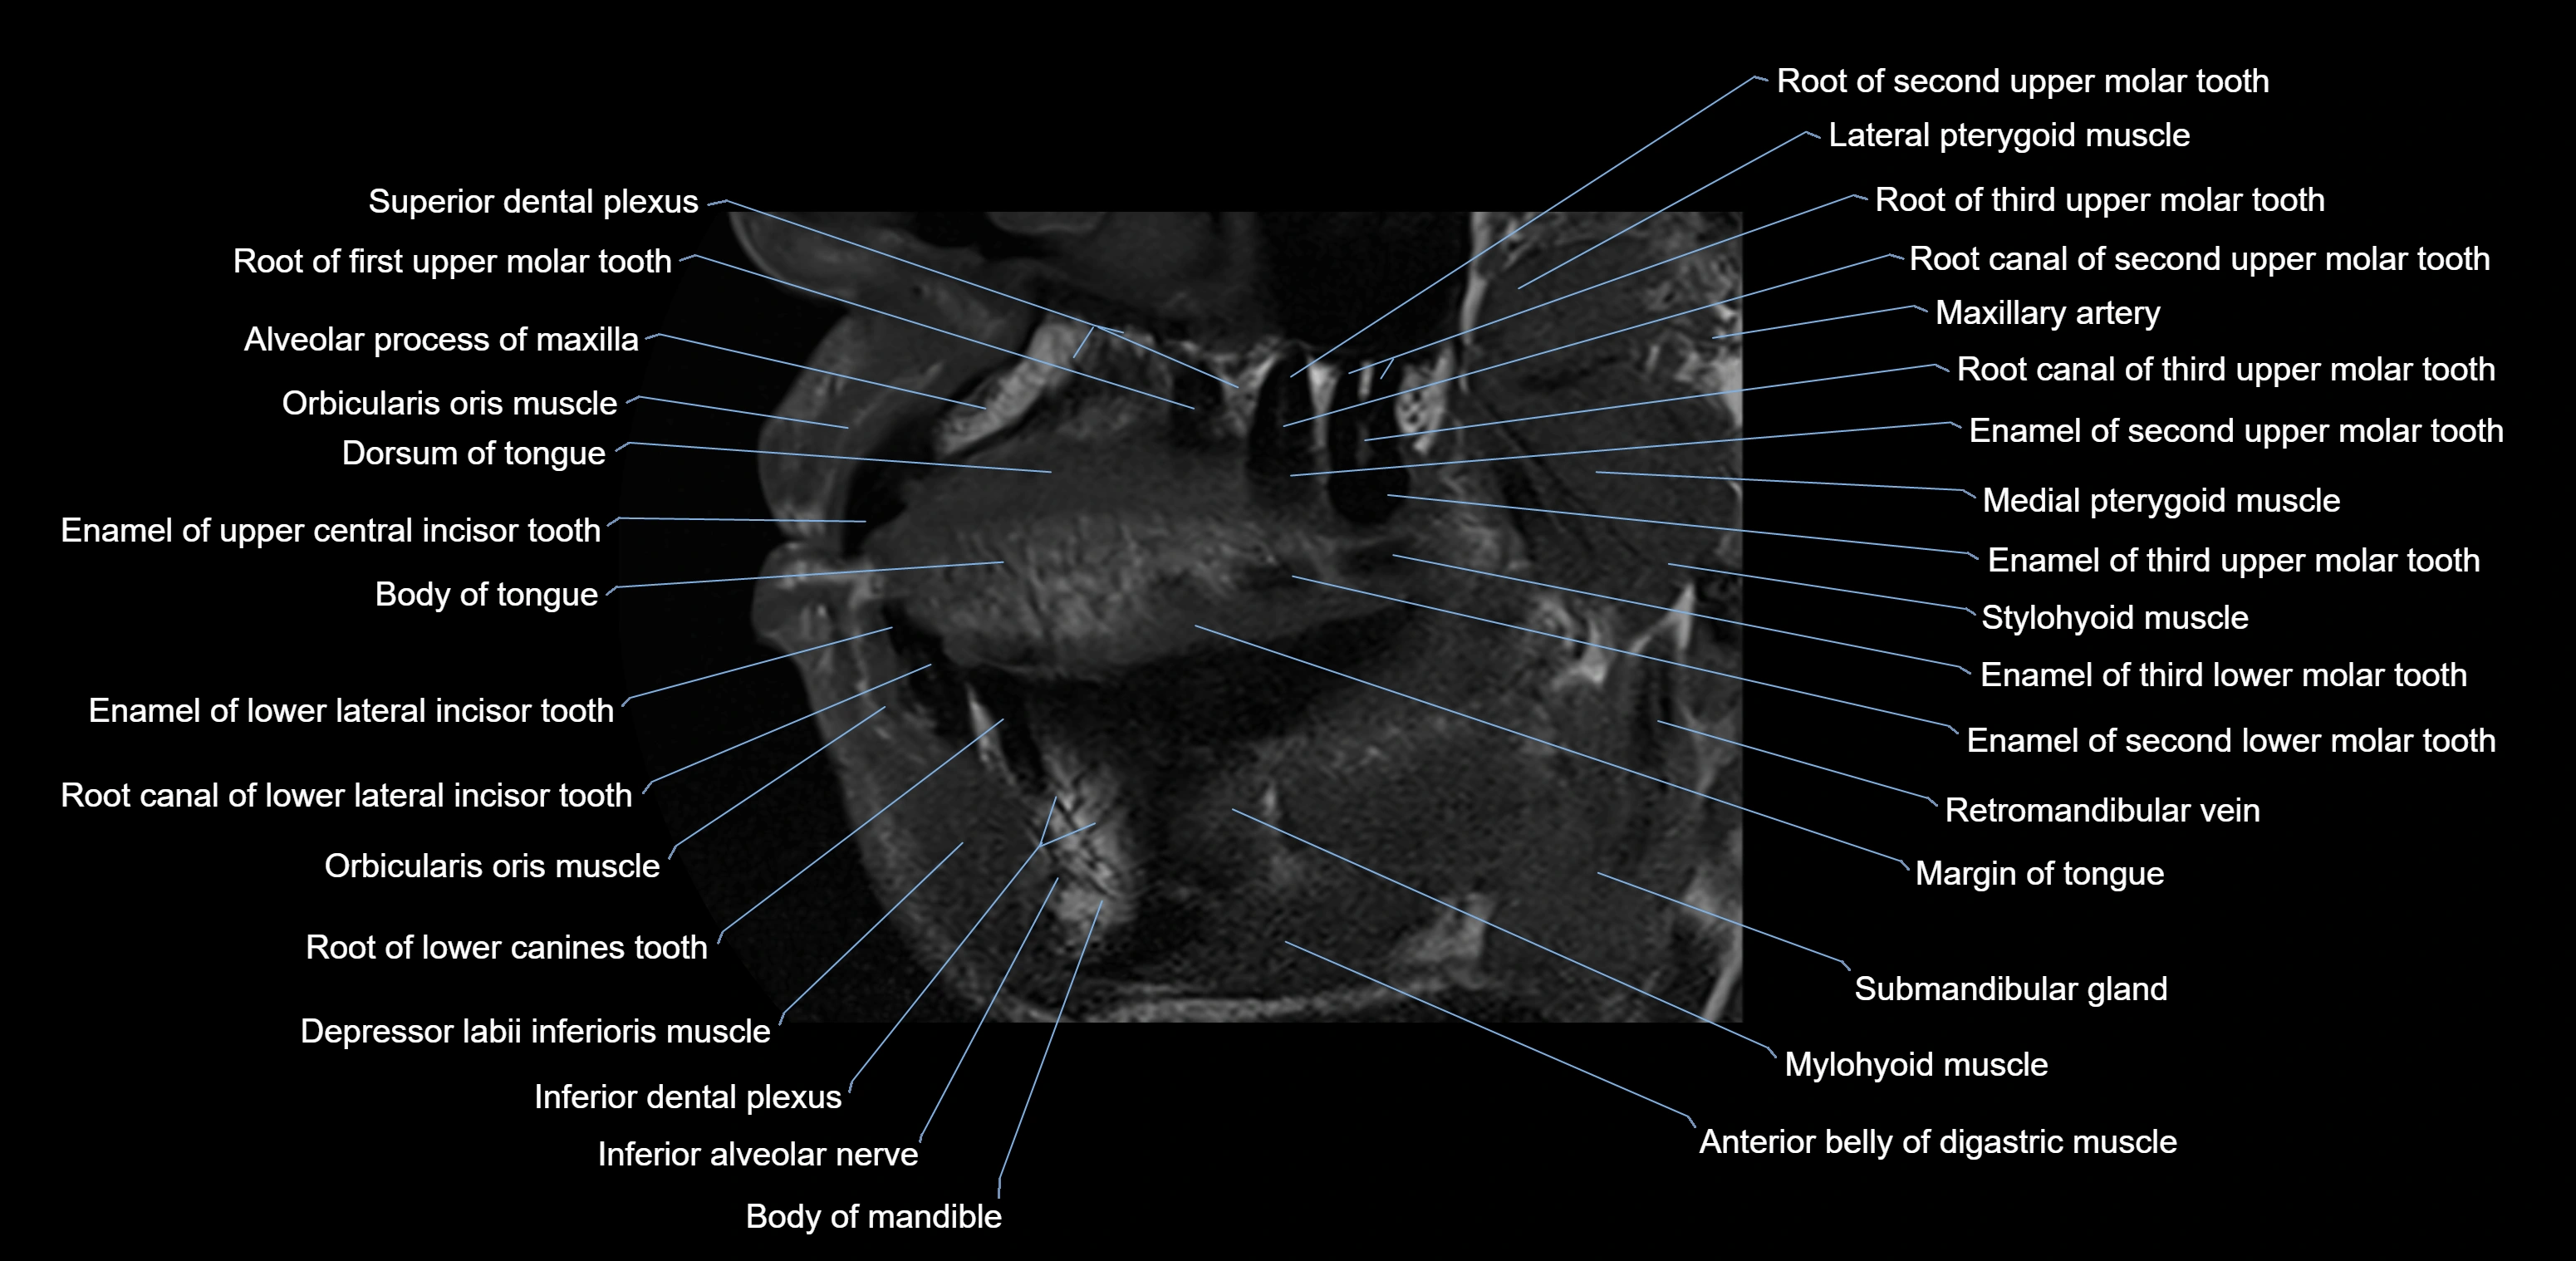

- Body of tongue

- Dorsum of tongue

- Inferior alveolar nerve

- Mylohyoid muscle

- Orbicularis oris muscle

- Superior dental plexus